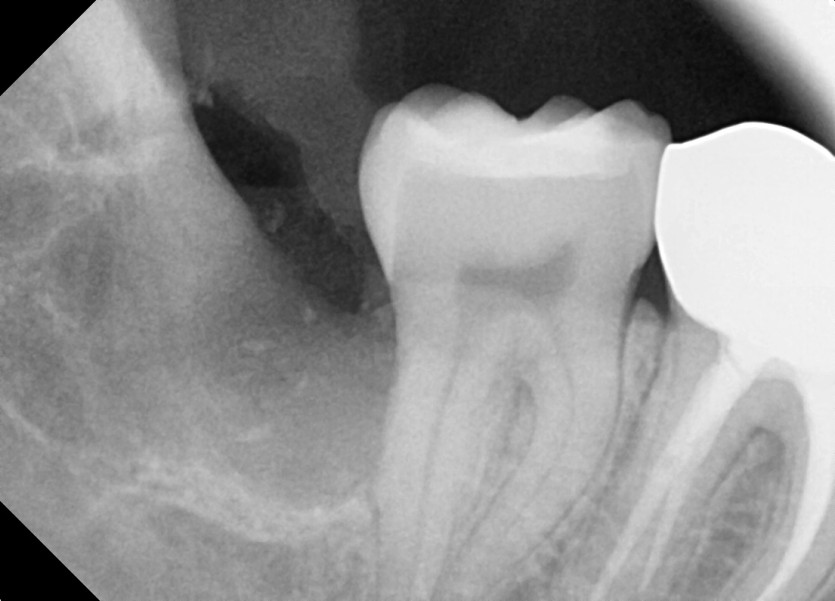

#48 사랑니 발치

구강 외과 전문의가 당일 발치했습니다.